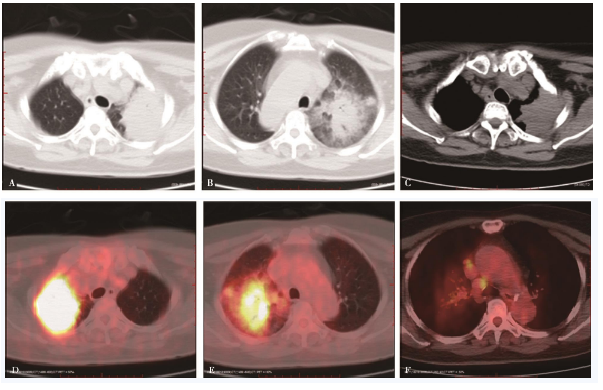

右肺上叶尖段不规则肿块,大小约5.8cm×5.1cm,边缘分叶状、毛糙、模糊,内见少许支气管气相,放射性不均匀增高,SUVmax约10.7,肿块周围多发模糊云雾状斑片影,放射性略增高。右肺门及纵隔内气管旁、上腔静脉前多发淋巴结肿大,最大直径约1.1cm,放射性轻度增高,SUVmax约3.4(图1)。

图1右肺寄生虫感染

A、B.右肺上叶不规则肿块,内见支气管气相,肿块周围多发云雾状斑片影;C.肿块与胸膜宽基底相连,未见胸壁侵犯征象;D、E.肿块FDG代谢不均匀增高,实性部位为著,SUVmax为10.7;F.纵隔多发淋巴结肿大伴FDG代谢增高